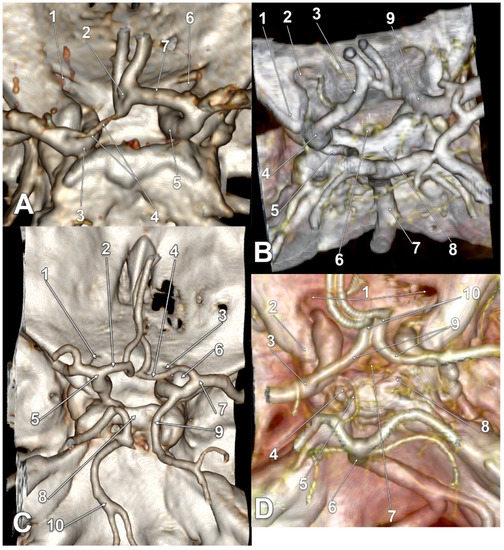

| Gender | Right Side | Left Side | Other Variations | Figure |

|---|---|---|---|---|

| M | type 3 IO A1 SCar | type 3 IO A1 SCar | high BA bifurcation | Figure 3A |

| M | type 3 IO A1 | type 3 IO A1 | Figure 2D | |

| M | type 2 IO A1 | type 1 IO A1 SCar | fenestrated AComA, hypoplastic left A1 | Figure 2A |

| M | type 2 IO A1 | type 2 IO A1 SCar | Figure 4C | |

| M | type 2 IO A1 | type 2 IO A1 | Figure 4A | |

| M | type 2 IO A1 | type 2 IO A1 | – | |

| M | type 2 IO A1 | type 2 IO A1 | Figure 5B | |

| F | type 2 IO A1 | type 2 IO A1 | rotated BA, left PCA displaced towards the ipsilateral A1 ACA | Figure 4D |

| F | type 2 IO A1 | type 2 IO A1 | duplicated AComA | Figure 4B |

| F | type 2 IO A1 SCar SClin | type 1 IO A1 | supraclinoid right A1 | Figure 2C |

| F | type 2 IO A1 | type 2 IO A1 | Figure 3D | |

| F | type 2 IO A1 | type 2 IO A1 | Figure 3B,C | |

| F | type 2 IO A1 | type 2 IO A1 | hypoplastic right A1 | |

| F | type 2 IO A1 SCar | type 2 IO A1 SCar | rotated AComA, hypoplastic right A1 | Figure 5A |

| F | type 2 IO A1 | type 2 IO A1 | rotated BA, left PCA displaced towards the ipsilateral A1 ACA | Figure 5C |

| F | type 1 IO A1 | type 2 IO A1 | left bihemispheric ACA | Figure 2B |